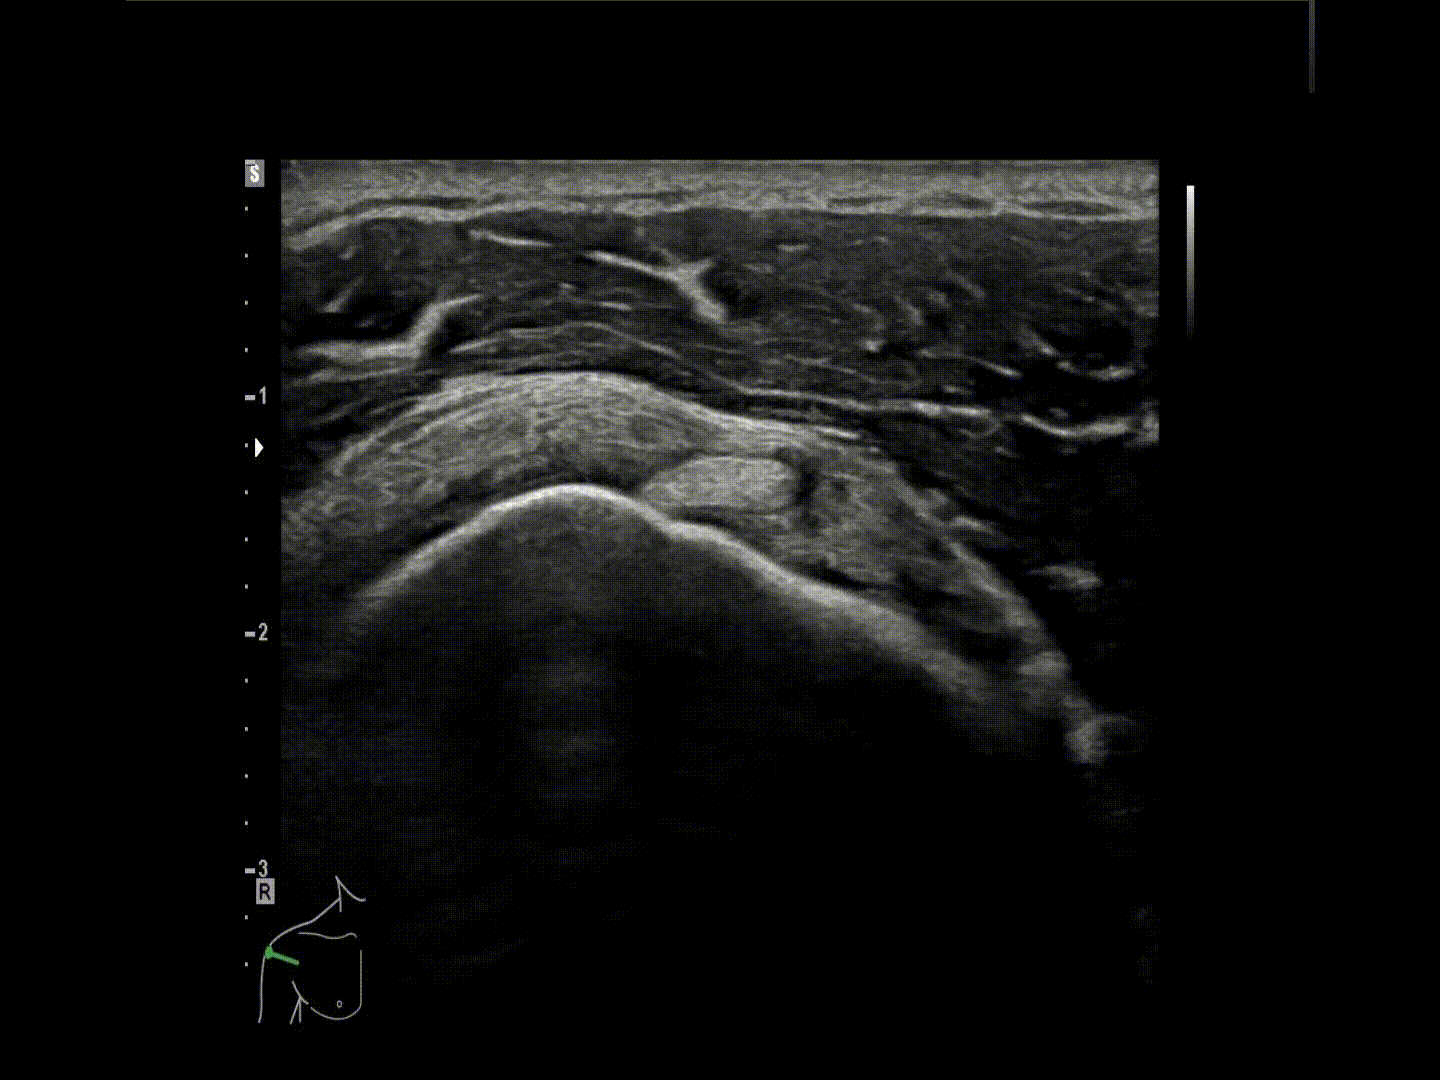

19 september heb ik in het Medisch Centrum Leeuwarden een opfrisser gegeven over echografie van het schouder. Nieuwe inzichten en benadering van het onderzoek zijn aan de orde geweest. Een uur lang hebben we de theorie behandeld met de bicepspullye en het belang van het dynamisch onderzoek met alle verschillende impingementtesten. Hierna zijn we naar het echotoestel gegaan voor een demo en hands-on training.